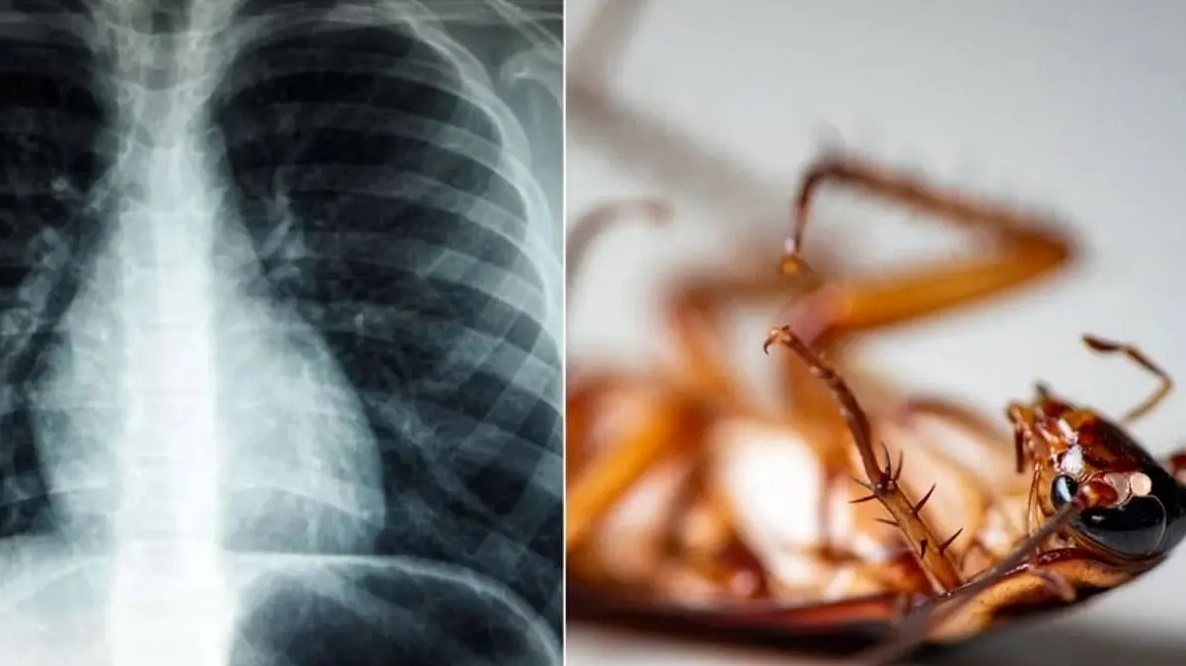

باورنکردنی؛ سوسک ۴ سانتیمتری که در ریه یک هندی زندگی میکرد

پزشکان اعلام کردند یک سوسک زنده را از داخل ریه یک مرد هندی خارج کردند.

زیسان: پزشکان در هند، سوسکی چهار سانتیمتری را از داخل ریه یک بیمار که به دلیل مشکلات تنفسی به بیمارستان مراجعه کرده بود، خارج کردند. این بیمار ۵۵ساله به بیمارستان ایالت کرالا مراجعه و اعلام کرد شرایط مناسبی ندارد. مشکلات تنفسی این فرد باعث شد پزشکان برونکوسکوپی را برایش تجویز کنند تا بدین ترتیب یک سوسک چهار سانتیمتری در ریه او مشاهده شود.

به گفته پزشکان، ظاهراً سوسک از طریق لولهای که قبلاً در گلوی این مرد برای رساندن اکسیژن ایجاد شده بود، وارد شش او شده است. به نوشته رسانهها، سوسک بعد از تلاشی چندساعته از ریه بیمار خارج شد.